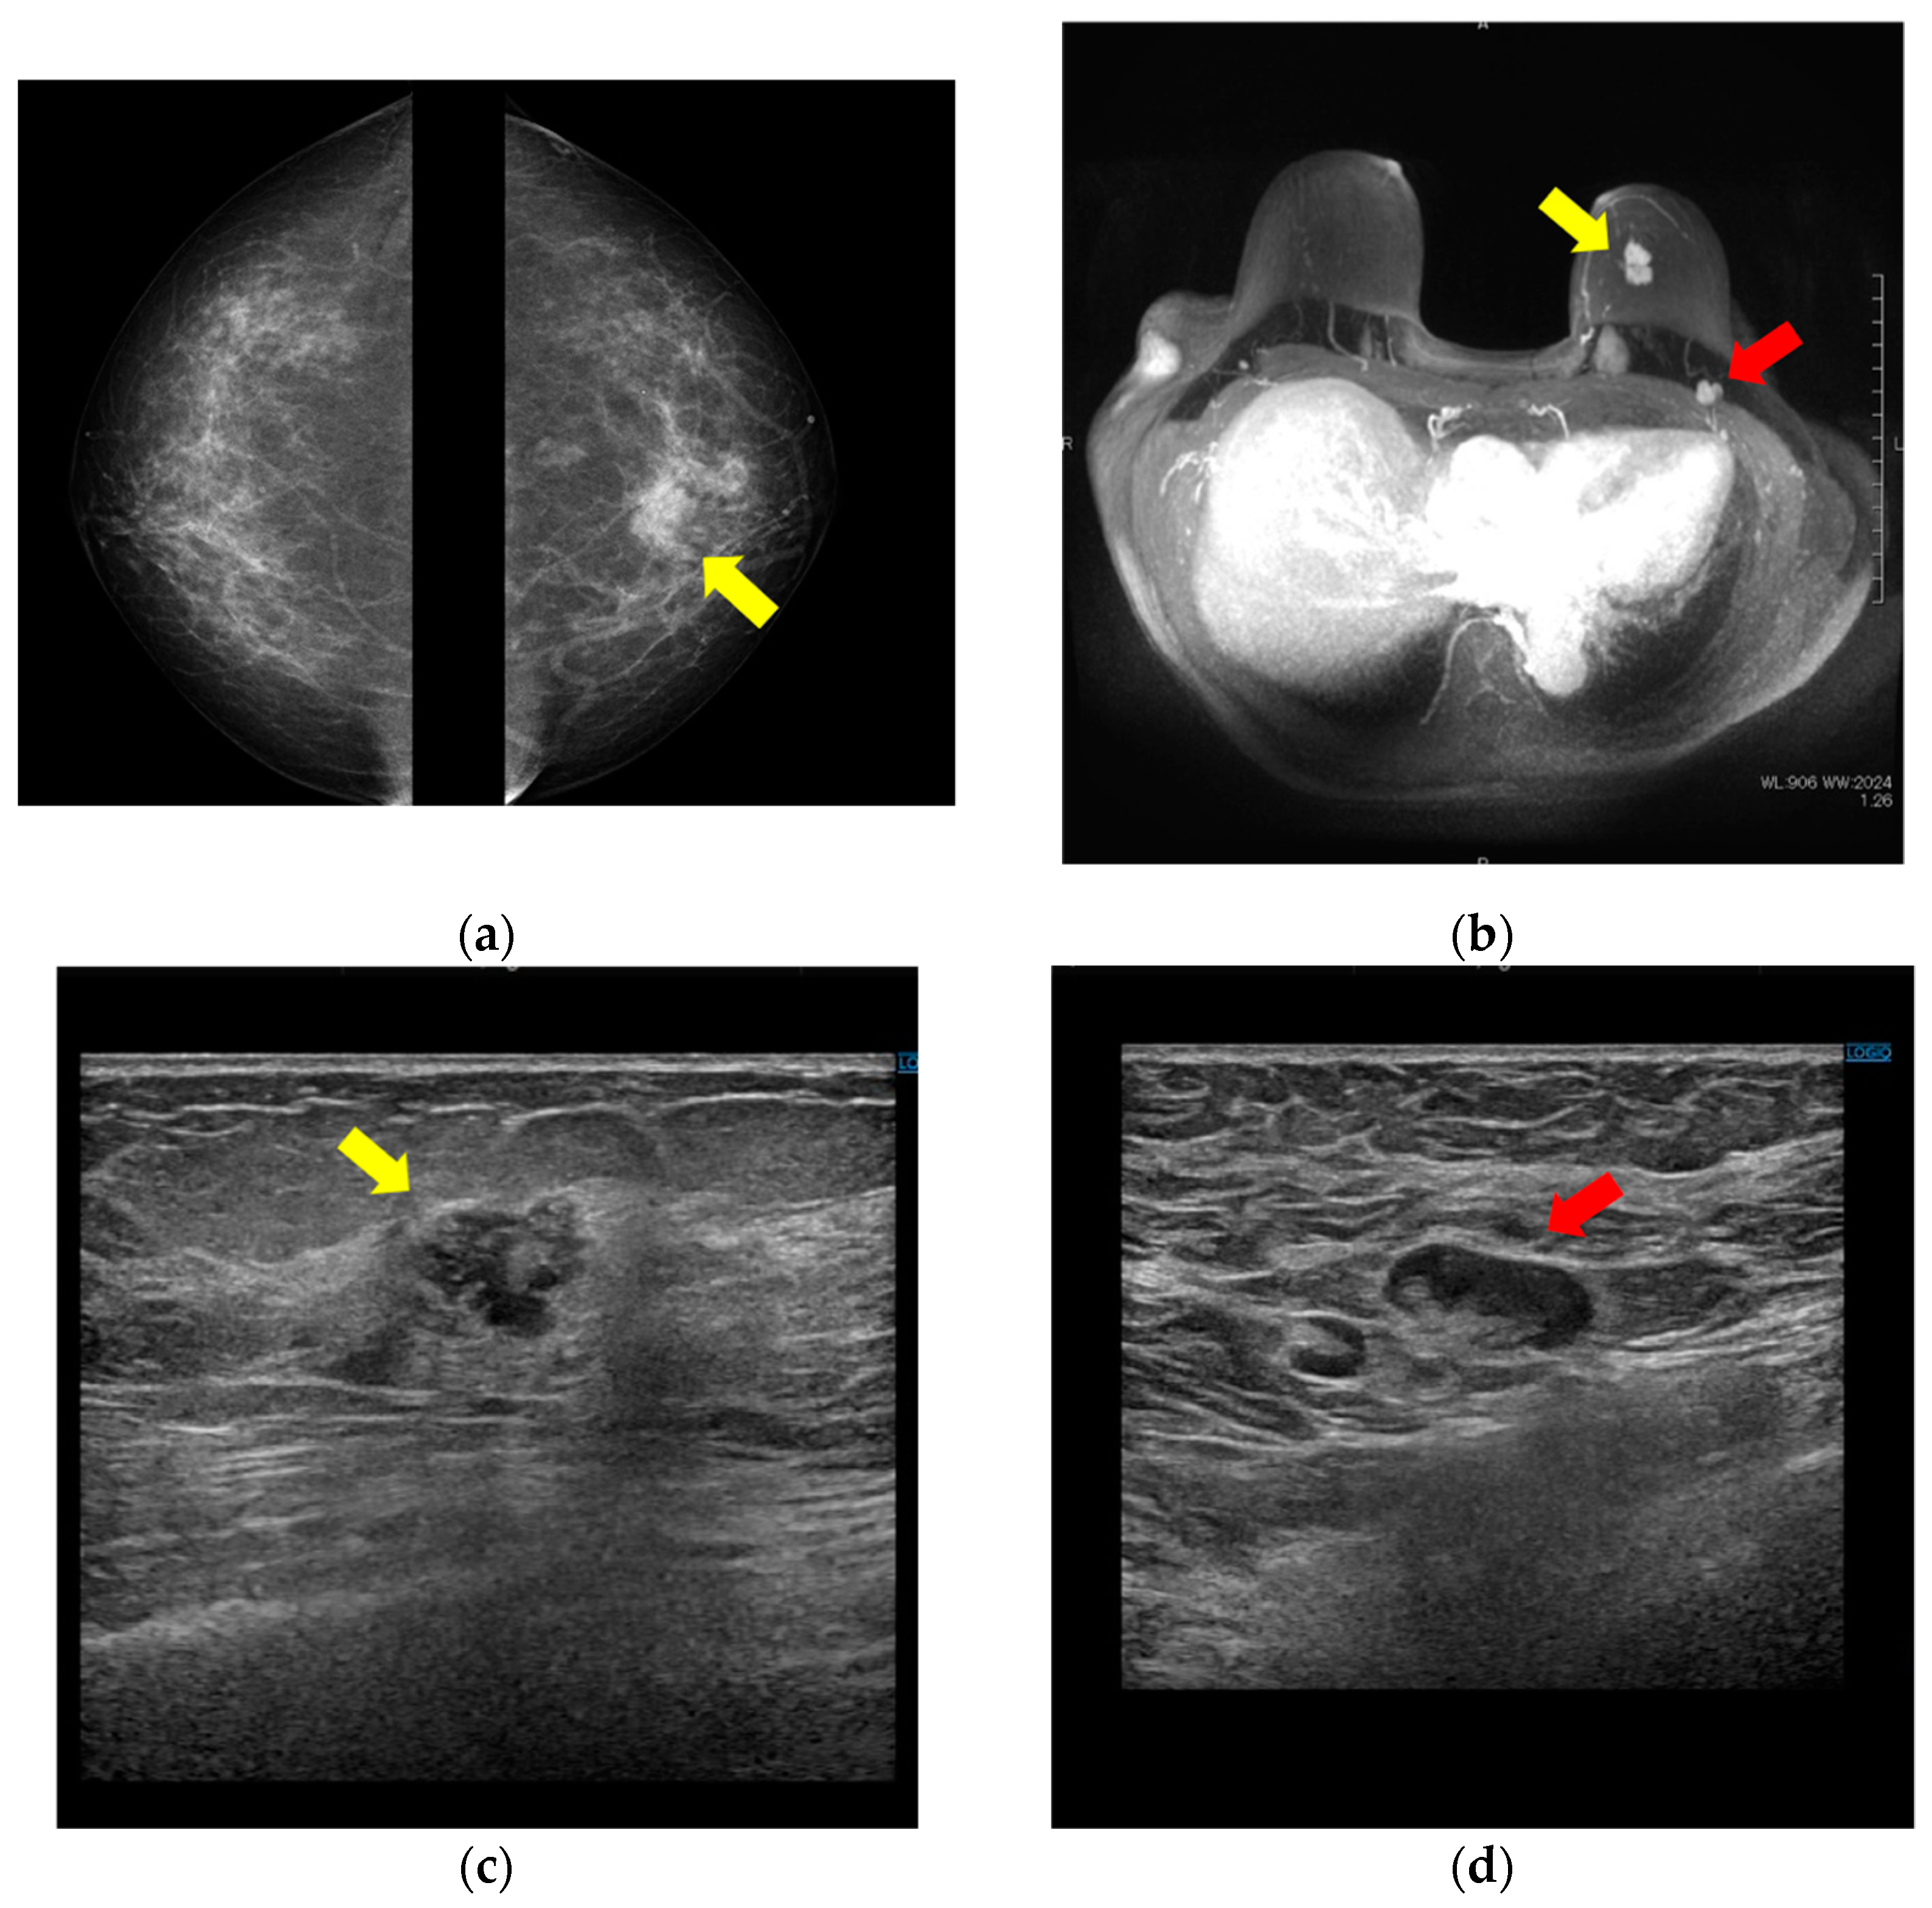

A woman in her 70 s (gravida 3, para 3) presented at our hospital for uterine tumor surgery. She had no relevant medical or family history. Preoperative screening CT revealed a left breast tumor and an enlarged left axillary lymph node, so she was referred to the breast surgery department. Mammography showed an irregular mass with an indistinct margin in the upper left breast (Figure 1a). MRI revealed an irregular mass in the left breast that showed contrast enhancement with a fast-washout pattern (Figure 1b). Ultrasonography showed an irregular hypoechoic tumor in the left breast (Figure 1c) and an enlarged lymph node with a thickened cortex in the left axilla (Figure 1d).

Figure 1.

Breast mass and axillary lymph node on mammography, MRI, and ultrasound. (a) Bilateral mediolateral oblique mammogram demonstrates a 20 mm irregular mass with indistinct margin in the upper area (yellow arrow). (b) MRI shows a 29 mm irregular mass that showed contrast enhancement with fast-washout pattern in the upper area of the left breast (yellow arrow) and enlarged lymph nodes in the left axilla (red arrow). (c) Ultrasonography reveals a 17 mm irregular hypoechoic tumor in the upper area of the left breast (yellow arrow) and (d) enlarged lymph nodes with thickened cortex in the left axilla (red arrow).